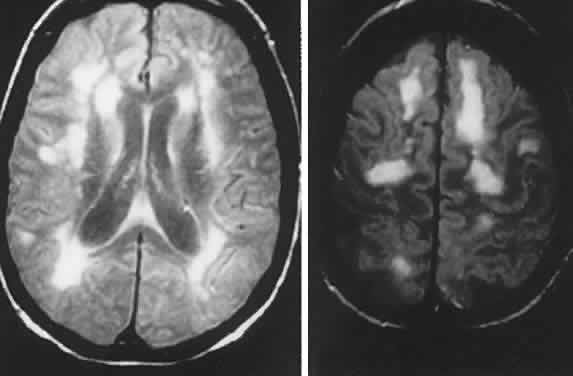

Neuroimaging in tuberous sclerosis demonstrates subependymal (periventricular) nodules, calcifications, and parenchymal hamartomas (cortical tubers); although calcifications are difficult to discern, MRI is considered a better screening procedure.150

NEUROFIBROMATOSIS